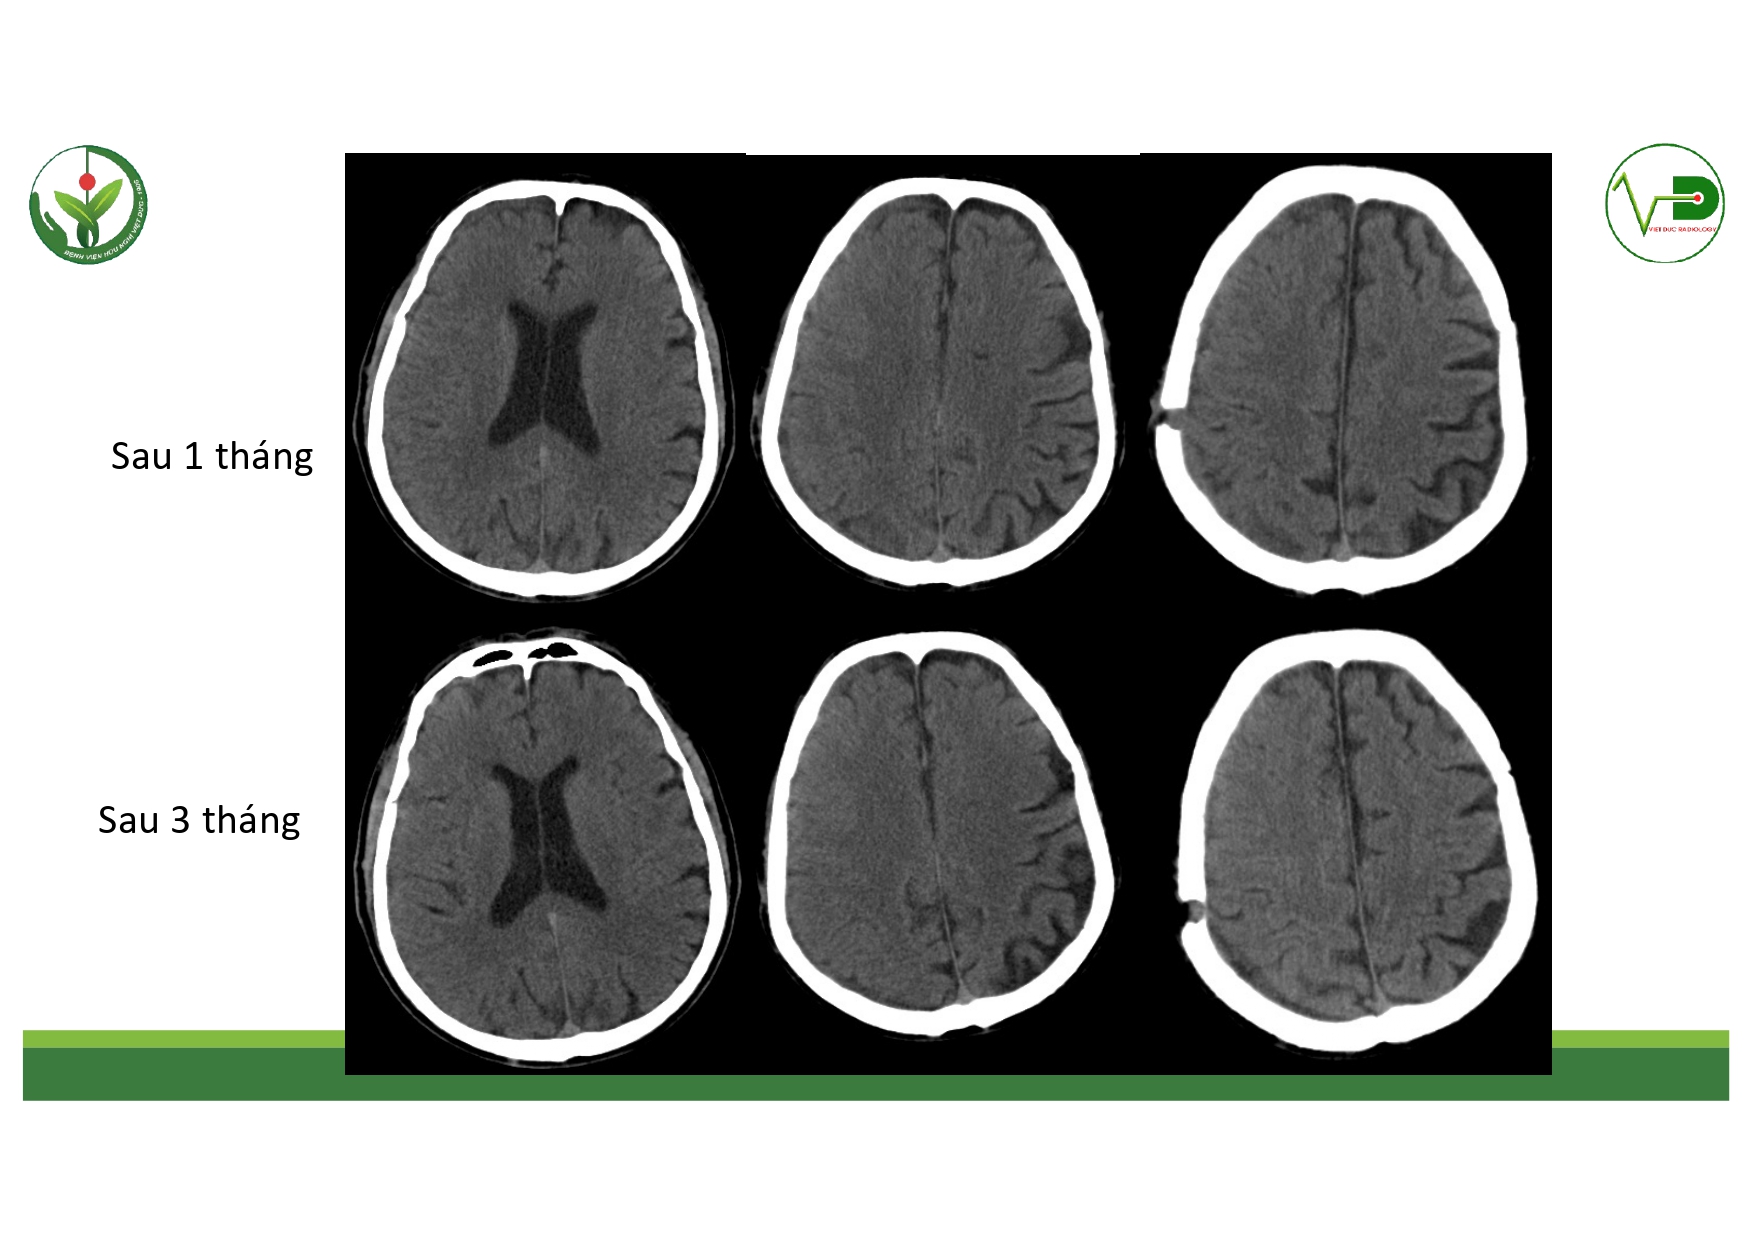

| 13:30 - 14:10 | Surgical management of skull base trauma Endovascular Management of Post-Traumatic Intracranial Vascular Lesions | Assoc. Prof. Nguyen Trong Yen Dr. Nguyen Ngoc Cuong | |

| 14:10 - 15:10 | DEBATE 2 | Recurrent chronic subdural hematoma– surgical or endovascular intervention? Surgical: Assoc. Prof. Duong Dai Ha Endovascular: Assoc. Prof. Le Thanh Dung | Moderator: Prof. Christian Matula Assoc. Prof. Duong Dai Ha | |

| 15:10 - 16:10 | Interactive Case Demonstration and Discussion II: ~20 minutes each, (5 minutes presentation followed by 15 minutes discussion) Practicals: How I am doing it? Participants present case presentations about how they do it? The faculty comment on and discussion. 1. Endoscopic approach in post-traumatic CSF leakage - Dr. Nguyen Thanh Xuan 2. Endovascular approach in CCF - Assoc. Prof. Le Thanh Dung | Prof. Christian Matula International & local faculties Participants | |